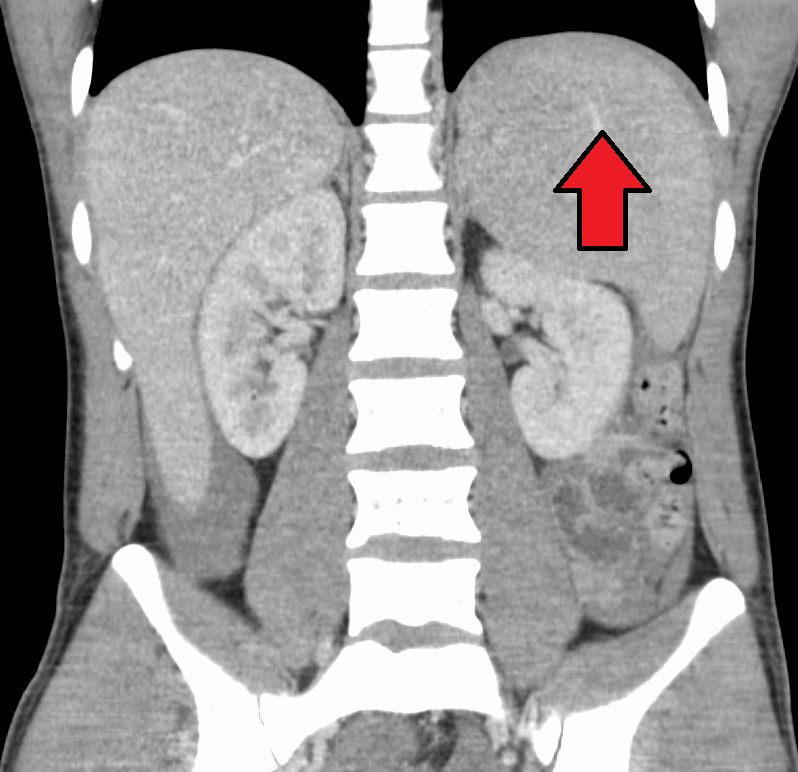

대부분의 감염성 단핵구증은 자연적으로 회복되지만, 드물게 합병증이 나타날 수 있다. 비장 파열, 용혈성 빈혈, 수막염, 뇌염, 횡단척수염, 길랭-바레 증후군 등이 발생할 수 있다.[26][63][64][43][65]비장 비대는 발병 2~3주차에 흔하게 나타나지만, 신체 검사로는 뚜렷하게 나타나지 않을 수 있다. 드물게 비장 파열이 발생할 수 있다.[26] 또한 약간의 간 비대증이 나타날 수 있으며,[23] 황달은 간혹 발생한다.[30][27]

비장 비대와 경부, 겨드랑이, 서혜 림프절의 림프절 종창은 감염성 단핵구증 진단을 의심하는 데 가장 유용하다. 반면에 경부 림프절 종창이 없고 피로가 나타나지 않는다면 감염성 단핵구증이 아니라고 생각할 수 있다. 비장 비대를 감지하는 신체 검사의 무감도는 감염성 단핵구증에 대한 증거로 사용해서는 안 된다는 것을 의미한다.[23] 신체 검사에서 구개의 점상 출혈이 나타날 수도 있다.[23]4. 2. 혈액 검사

비장 파열의 위험을 줄이기 위해 전문가들은 질병 발병 후 최소 3~4주 동안 또는 치료 의사가 결정한 비장 비대 소실 시점까지 접촉 스포츠 및 기타 격렬한 신체 활동, 특히 복부 압력 증가 또는 발살바 수기 (예: 조정 또는 역도)를 피하도록 권고한다.[23][52] 간비종이 심한 경우에는 복부에 충격을 받아 비장 파열이 일어난 사례도 있으므로 안정이 필요하다. 소아 등, 인두통이나 전신 권태감으로 인해 경구 섭취가 불량해진 경우에는 입원하여 수액을 투여할 필요가 있다.